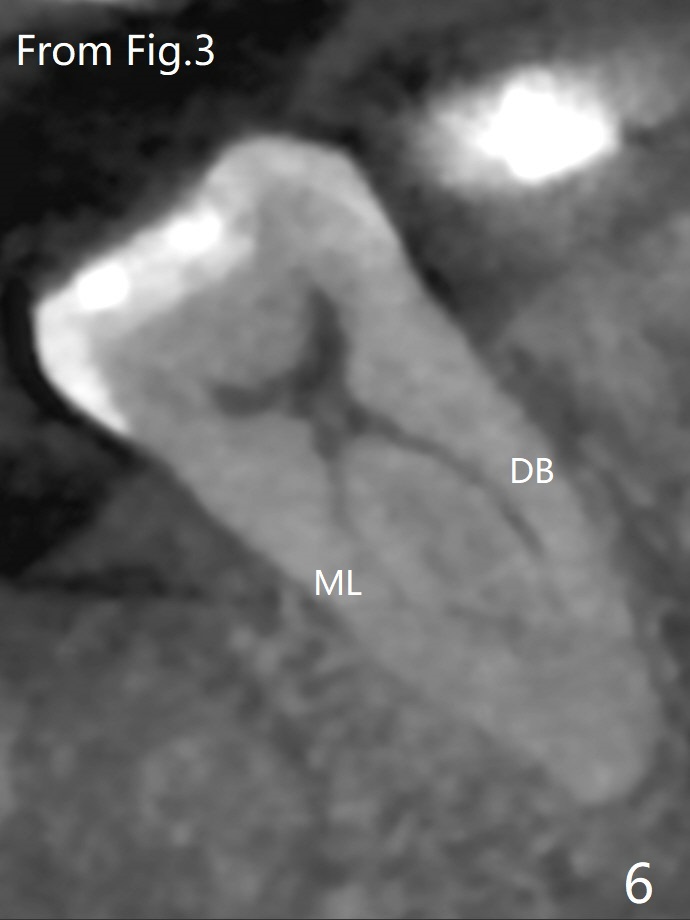

A 61-year-old man may have referral pain between #17 and 18. The canals at #18 are narrower than those at #17 (Fig.1-3). If #18 needs RCT, blocks should be removed (Fig.4-6 vs. 4'-6').